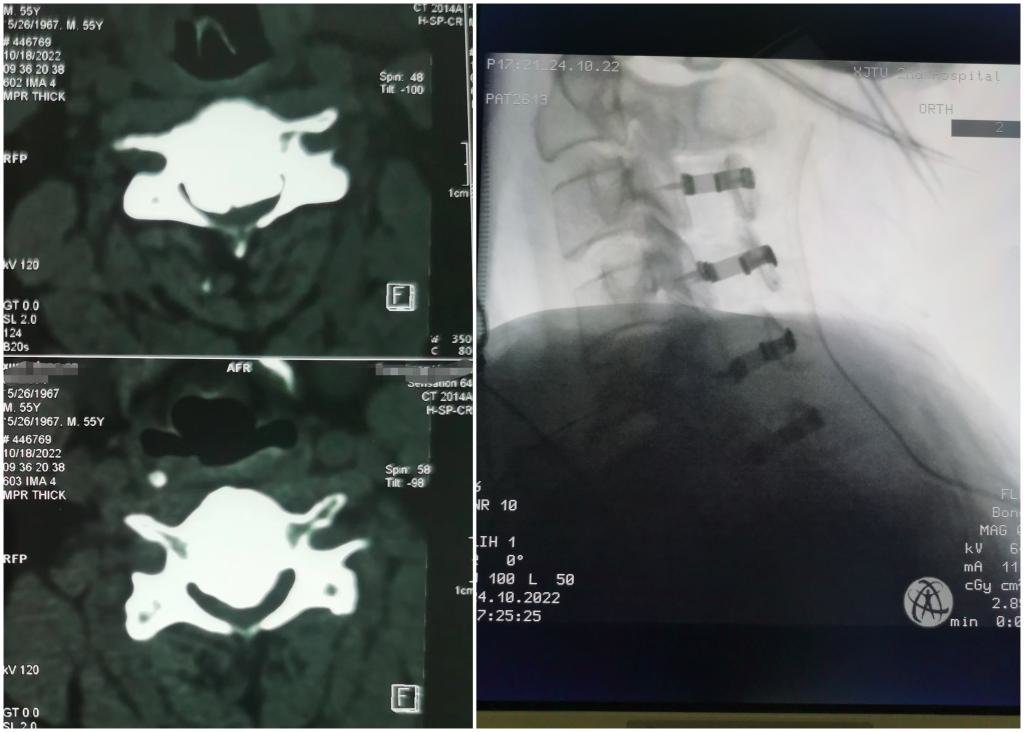

2022年10月24日,由张纯主任医师主刀,王伟卓副主任医师、刘若西主治医生配合,李伟教授、张鹏、代志明团队麻醉,王芳术中肌电图监测。手术如期开展,但麻醉后,肌电图报告患者运动体感诱发电位波幅非常微弱,给神经监测带来极大难度,增加了手术难度。为了患者获得救治,张主任团队凭借多年复杂颈椎手术经验,迎难而上,精准轻柔操作,当椎板打开、脊髓减压后,患者肌电图波幅逐渐出现,大家顿感轻松,如释重负,手术持续约三个小时,顺利完成。